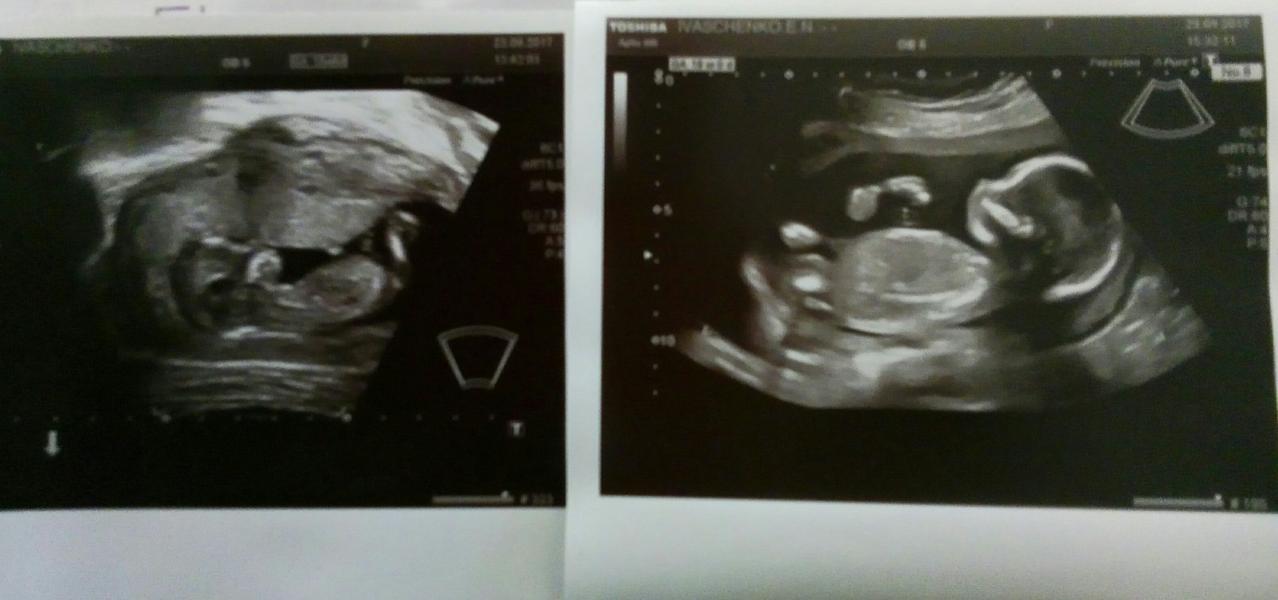

Вчера сходила на второе узи. Мальчугана нам подтвердили, чему лично я безмерно рада. Будет у Тимурчика братик. Теперь у нас уже 2 фотки нашего малыша: слева 12+6, справа 18+3